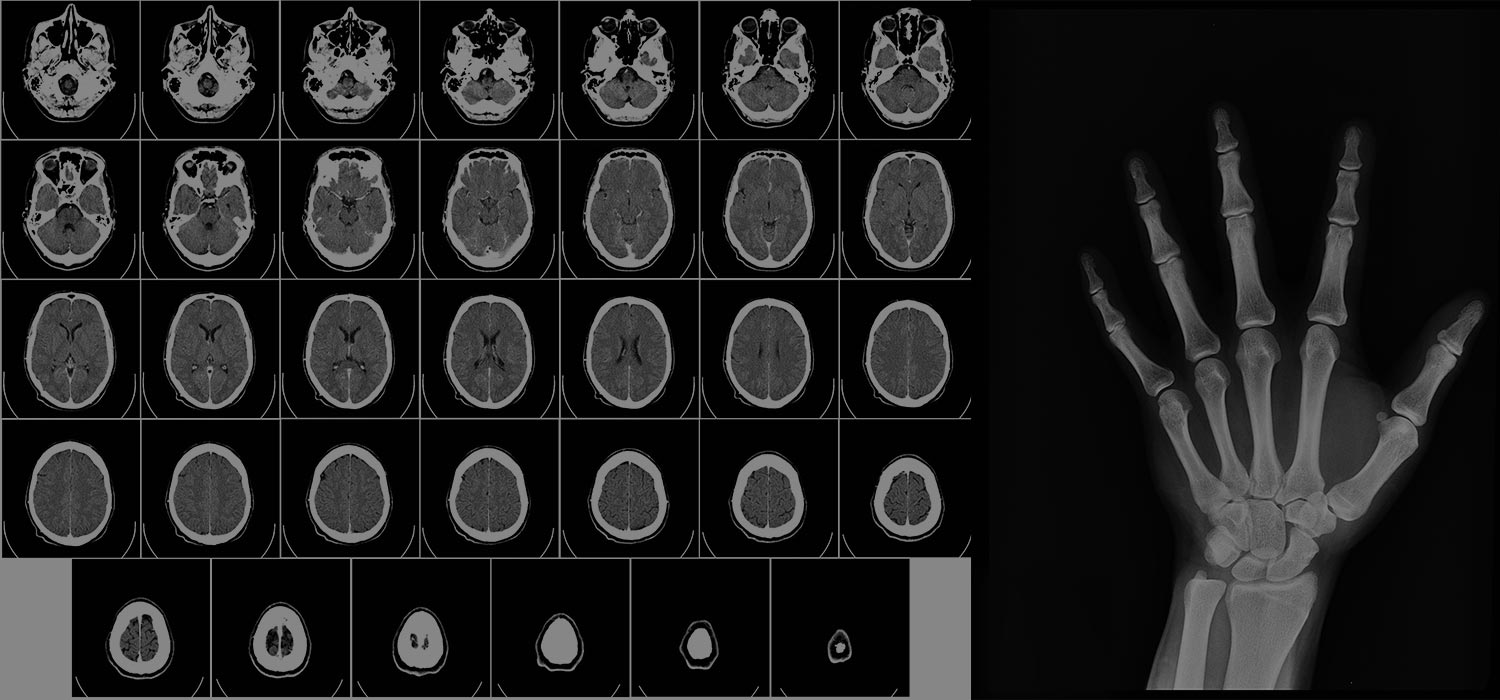

X-ray diagnostics have long been a cornerstone in medical imaging, enabling the...

Imaging modalities, such as X-rays and CT scans, are commonly used in medical diagnosis and treatment. These...

Artificial intelligence (AI) is rapidly becoming a game-changer in the field of medicine, particularly in the area of imaging...

Artificial intelligence (AI) is commonly used for support and efficiency in the medical community. Al has evolved...